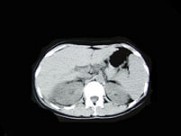

- 多项选择题女,33岁, 右胁腹痛7天,尿检可见大量的脓细胞, CT平扫+增强如图所示,下列说法正确的是 ( )

A、右肾体积增大,其内可见类圆形低密度病灶

B、增强扫描可见该病灶不均匀强化,其内有无强化的坏死灶

C、右肾病灶边界模糊不清

D、考虑为右肾囊肿合并感染

E、考虑为右肾脓肿